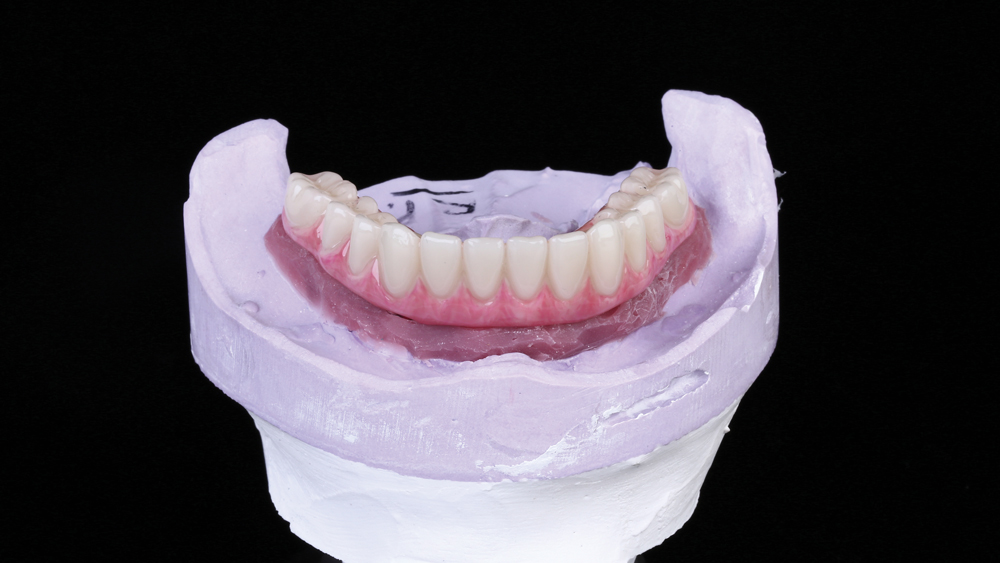

This patient was unhappy with the esthetics of her existing upper denture as well as the discomfort and instability caused by her loose-fitting mandibular partial denture. Although her concerns with the maxillary denture could be addressed with a new, more esthetic appliance, she preferred implant treatment for her mandible, where a fixed solution was needed to adequately restore function, stability and comfort.

Treatment plan:

The patient’s remaining mandibular teeth were extracted followed by immediate implant placement and delivery of a fixed provisional appliance. After integration of the implants, the prosthetic designs for the new upper denture and lower implant restoration were determined in tandem. Ultimately, the dual-arch restorations addressed the functional and esthetic challenges of the case while staying within the financial means of the patient, demonstrating the benefits of a flexible, multifaceted approach to restorative dentistry.